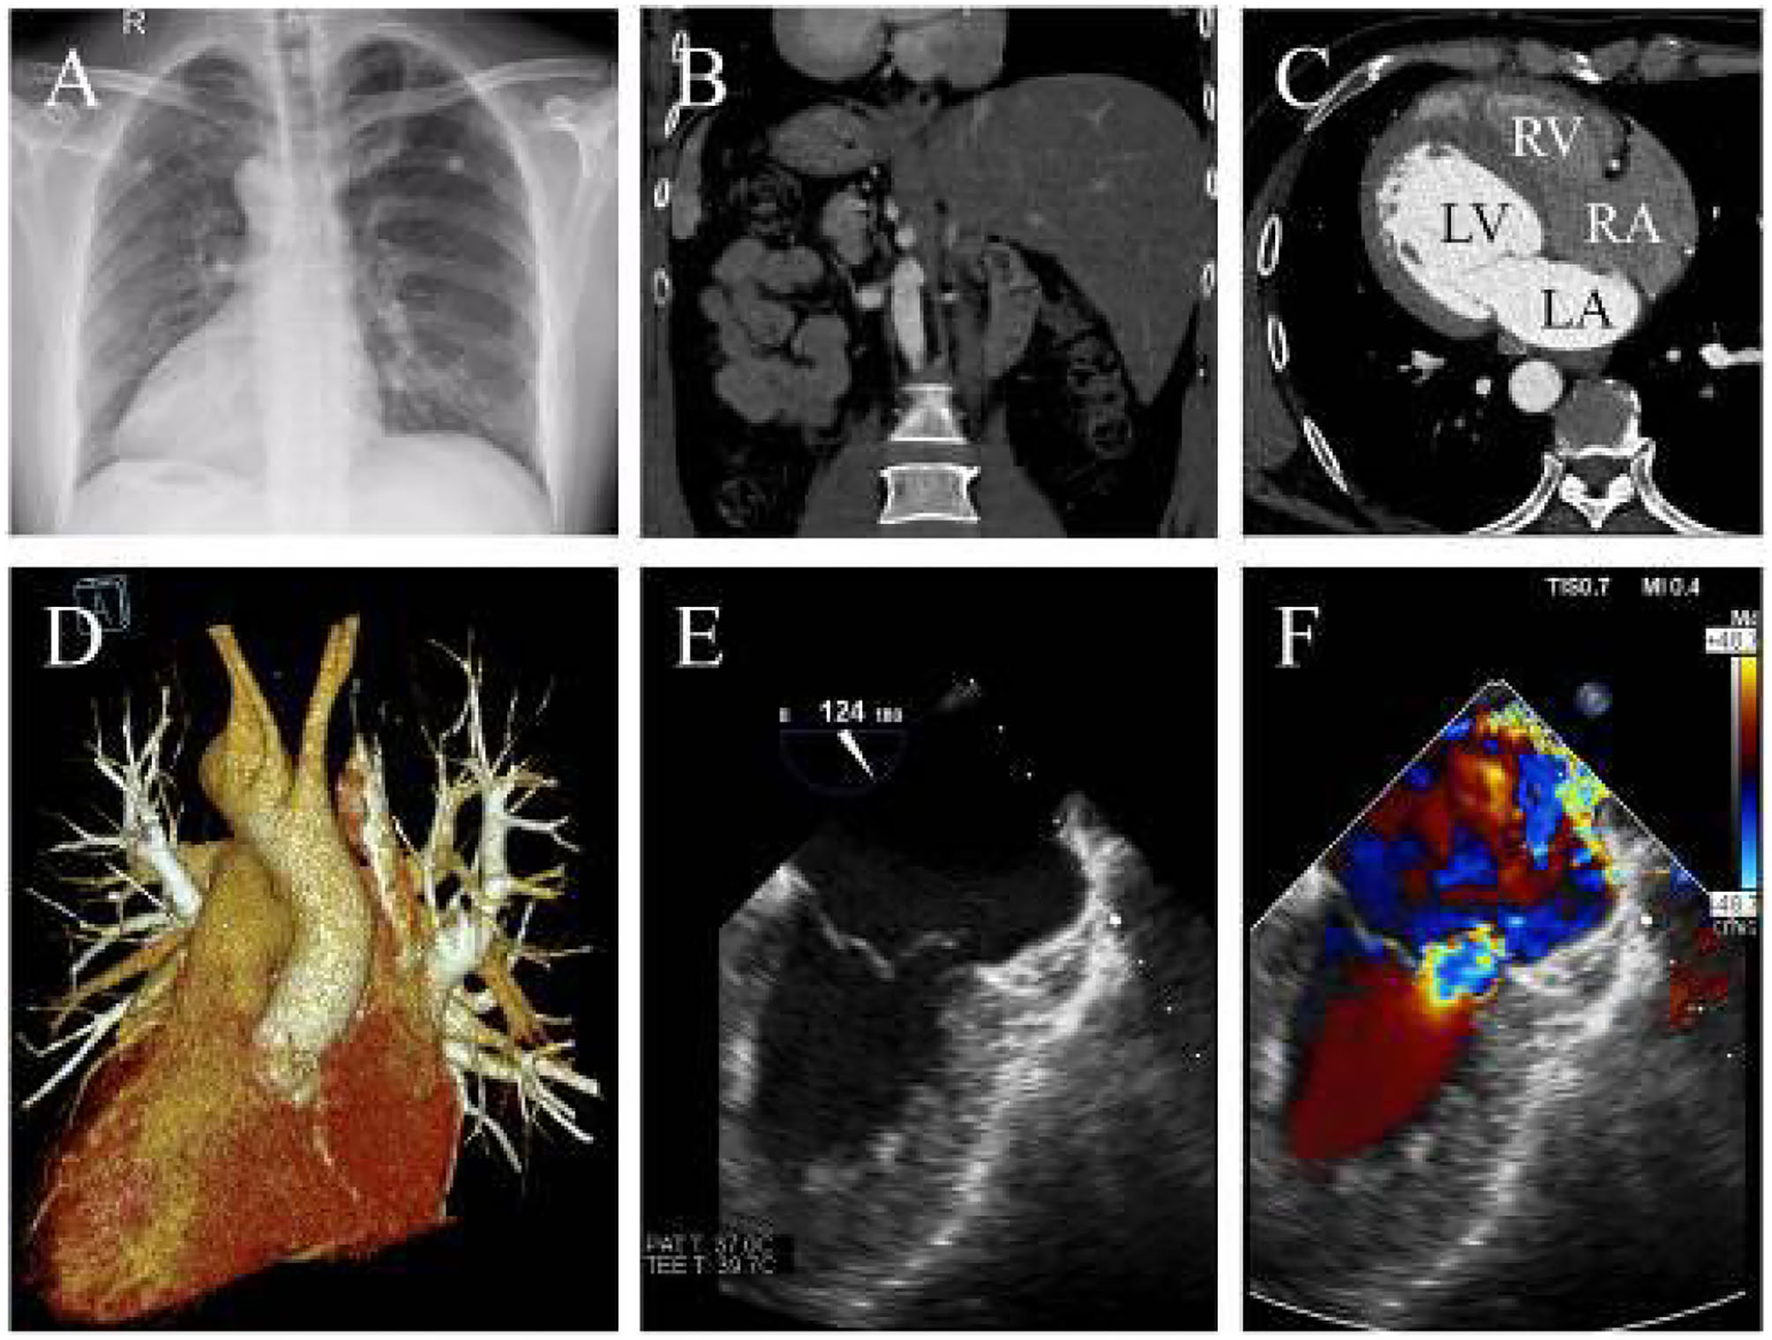

A 39-year-old man who complained of progressive exertional dyspnea and intermittent palpitation was referred to our department. He denied any familiar history of situs inversus dextrocardia or other cardiac health comorbidities. The patient, however, had occasional dizziness but denied any history of hypertension or cerebral infarction. Physical examination revealed a systolic blowing murmur (grade 3/6) at the fifth intercostal space lateral to the right midclavicular line. Chest roentgenogram and computed tomography (CT) showed dextrocardia with an enlarged silhouette and situs inversus totalis (Figures 1A,B). The anatomic diagnosis was mirror-image dextrocardia, L-loop ventricles, and typical related great arteries without associated congenital cardiac abnormalities (Figures 1C,D). Transesophageal echocardiography further revealed severe mitral valve regurgitation where the vena contracta was >0.7 cm and tricuspid regurgitation following annular dilation. The left atrium diameter was 5.8 cm without thrombosis formation (Figures 1E,F and Supplementary Video 1). A 24-h Holter monitoring demonstrated paroxysmal AF with a total burden of 165 min.

Figure 1. (A) X-ray indicates dextrocardia and cardiac enlargement. (B) CTA reveals transposition of the abdominal organs and (C) confirming L-loop ventricular orientation and concordant atrioventricular connections. (D) Three-dimensional CTA shows normal great artery development and connections. (E) The transesophageal echocardiography shows mitral chordae rupture and (F) severe mitral regurgitation (LA, left atrium; LV, left ventricle; RA, right atrium; RV, right ventricle).